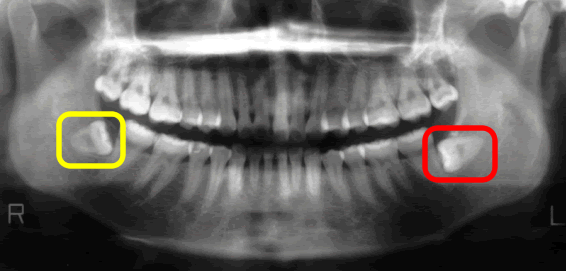

これ(下写真↓)は私の歯のレントゲン写真です。

「親知らず」というのは真正面から数えて8番目の歯になります。

「親知らず」というのは8番目の歯です。

それはパノラマレントゲンという大きいレントゲンを撮ればすぐに分かります。

このレントゲン写真は40代の方です。

8番目が親知らずです。

横に向いて生えていますね。

親知らずの手前の歯7番目、その手前の歯6番目、どうなっているでしょう?

6番目は斜めに倒れて、かつ、上に上がっていますね。

親知らずに押し上げられているんですね。